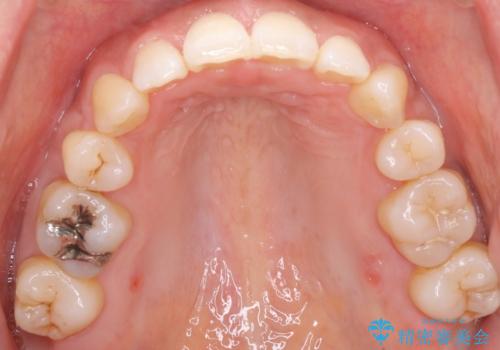

- 出っ歯がきになるとのことで来院されました。

上顎の前歯は前方に傾斜しており、下あごの前歯にもガタガタがありました。

上下左右の小臼歯を合計4本抜歯して矯正することとしました。

矯正を開始する前から歯肉退縮があり、悪化しないように注意しながら矯正治療を行いました。